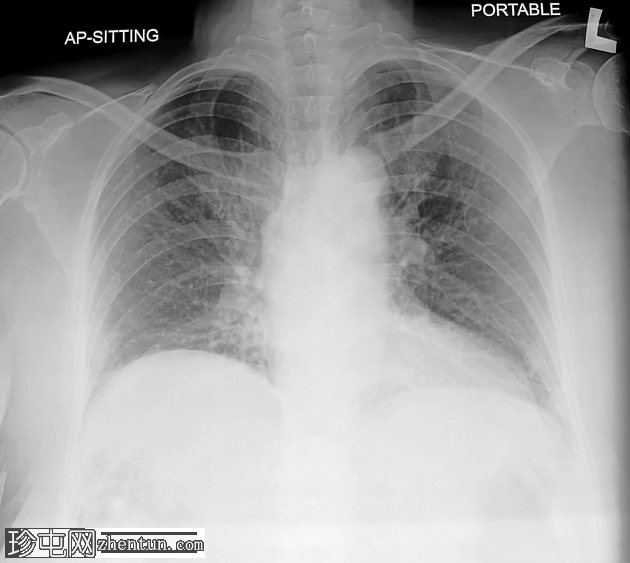

超声检查

肝胆系统

肝脏第6和第7段可见多个高回声气体腔,遮挡肝脏后部

肝脏其他部位形态及回声纹理正常

胆总管扩张,无结石,肝内胆管未见扩张

其他方面正常无游离液体

超声表现符合气肿性肝脓肿。数小时后进行的肝脏增强 CT 多期扫描显示气肿性肝脓肿破裂。